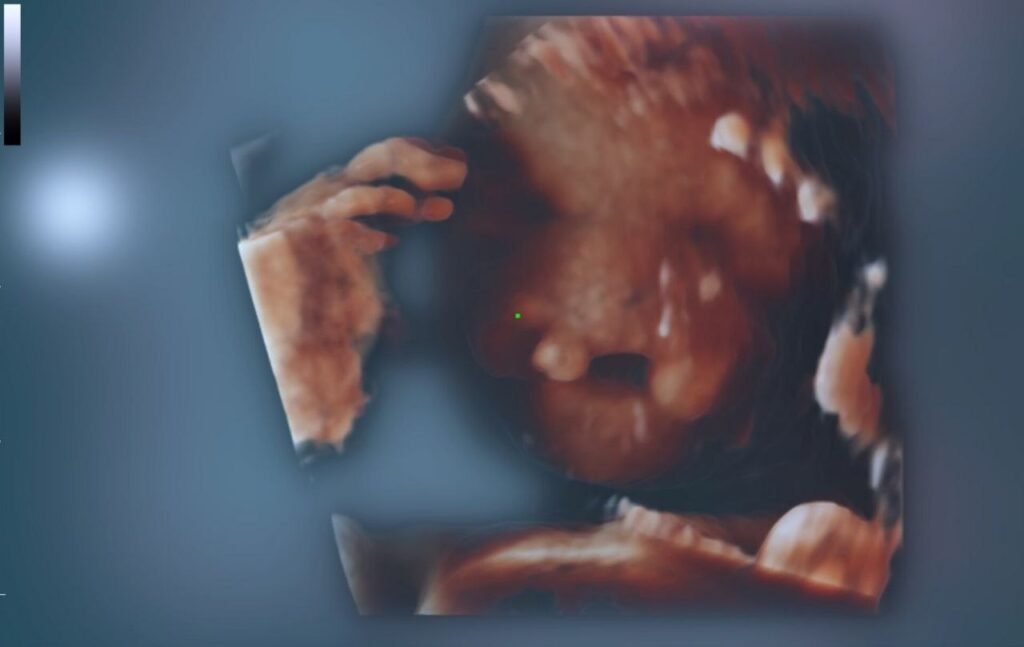

Microphthalmia fetal ultrasound

Antenatal ultrasound

Assessment and detection of microphthalmia antenatally is difficult and is often inferred from a small size of the orbit. There may or may not be evidence of concurrent hypotelorism.